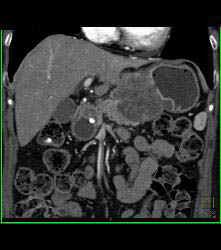

Antral Carcinoma With Adenopathy